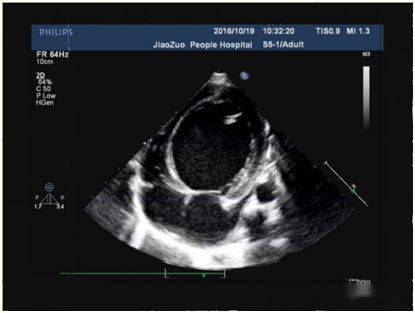

心内膜胶原弹力纤维增生症 (endocardial fibroelastosis,efe) 是指心